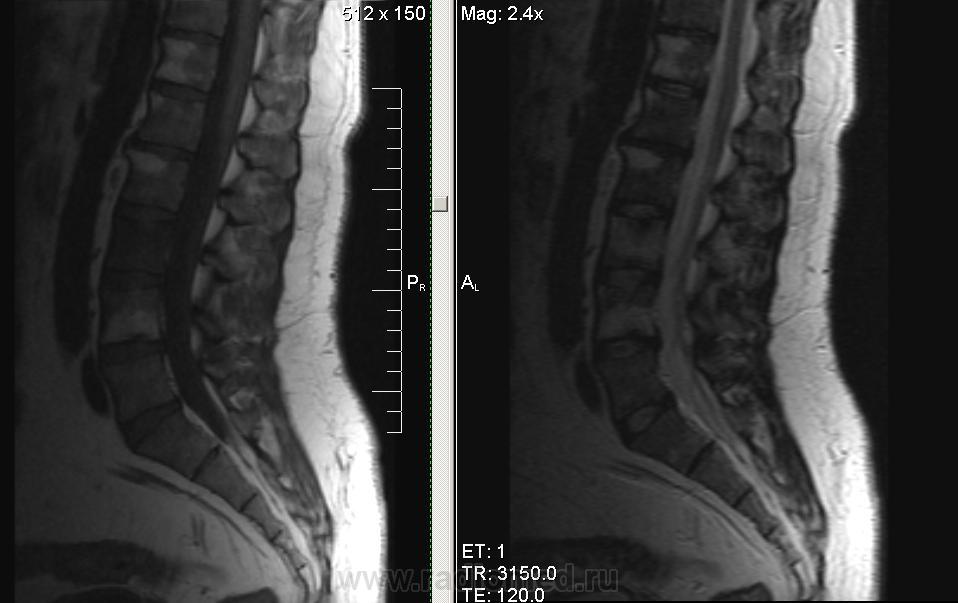

Мужчина, 1974г.р. В течении полугода боли в правой ноге, пояснице. Коллеги, подскажите, пожалуйста, что за системная болячка такая. В грудном отделе - то же самое.

серонегативная спондилоартропатия (?)

Ага, по ссылке Бехтерева.. Тока обычно изменения в области дугоотростчатых суставов и рёберно-позвонковых. У меня было первой мыслью, но суставов на представленных снимках нет.

Сакроилеит. Так что спондилоартрит наиболее вероятен. И боль в правой ноге понятна. Я если у молодых людей причины для корешковых болей не вижу, делаю программу на крестцово-подвздошные суставы. Единственно, в позвоночнике обычно бывает отёк костного мозга апофизов, дугоотростчатых и рёберно-позвонковых суставов.